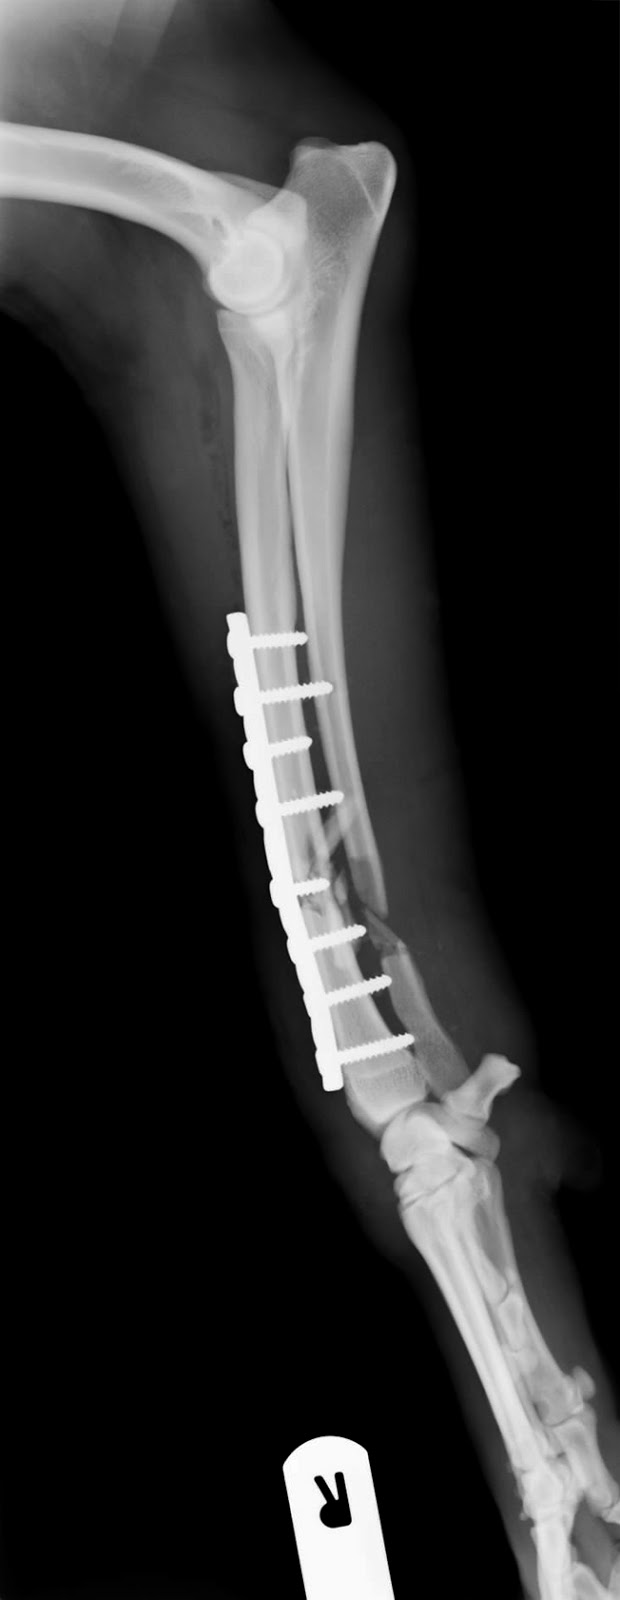

Web- Con desplazamiento y fractura del cuello quirúrgico sin desplazamiento (dos segmentos) - Con desplazamiento y fractura del cuello quirúrgico con desplazamiento (tres. WebTratamiento en fisioterapia de las fracturas de húmero: Dependiendo del tipo de fractura se optará por tratamiento conservador, inmovilización del brazo con.

WebPara las fracturas conminutas que afectan a la superficie articular, el reemplazo protésico total o parcial parece ser aceptado actualmente como tratamiento de elección 5, sin. WebCuando el dolor y las molestias disminuyen, se recomienda seguir un ejercicios de rehabilitación que te ayude a recuperar la movilidad previa. El tiempo de recuperación. WebEl mecanismo de fractura, el grado de osteoporosis o el trazo de la fractura pueden hacer que la posición natural del húmero se vea alterada en mayor o menor medida. Por. WebCon frecuencia el fragmento desprendido no se desplaza; el pronóstico es bueno y el tratamiento sólo requiere de inmovilizar el brazo en un cabestrillo por 2 a 3. WebEl brazo se inmoviliza para mantener la estabilidad de la fractura y proporcionar alivio del dolor durante la cicatrización. La consolidación de la fractura se. WebEl desplazamiento de los fragmentos casi siempre es moderado y no necesita de ninguna maniobra reductiva. Basta una simple inmovilización con un.

WebEl objetivo inicial en el tratamiento de fractura de troquiter es una recuperación estructural. La base de acelerar el proceso de recuperación de la estructura, es. WebEl tratamiento puede ser conservador o requerir de intervención quirúrgica. El objetivo principal es aplicar un plan de intervención fisioterapeútico en la fractura.